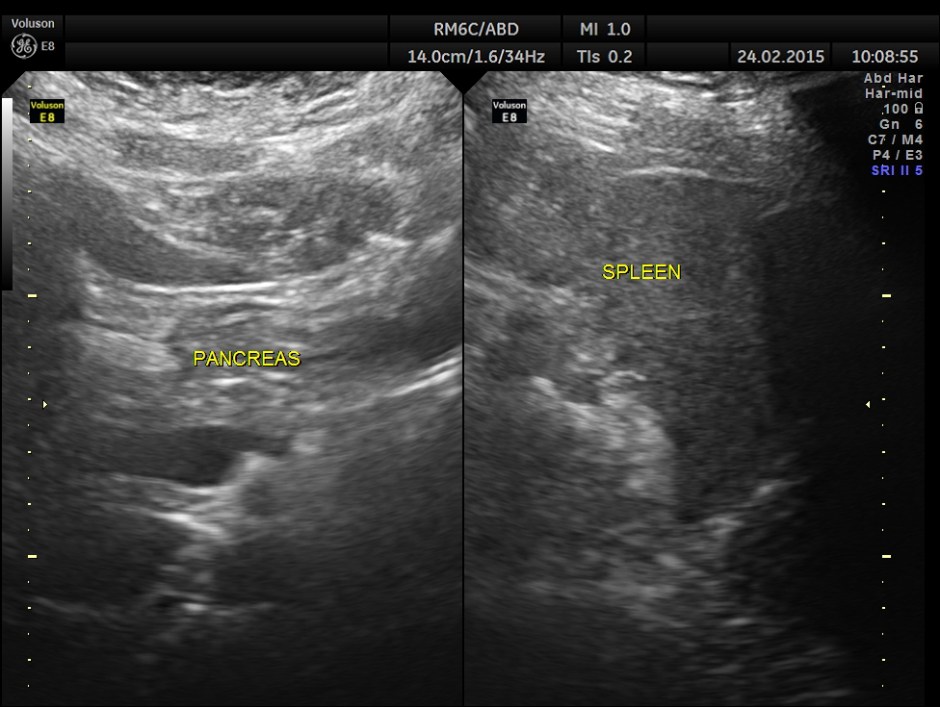

The patient was asked to take a fatty meal and report again and this was seen.The gall bladder has started to be filled up and was showing distension , contrary to what happens in a normal person.

2 hours after the meal the gall bladder was still distended and no gallstone was visualised .